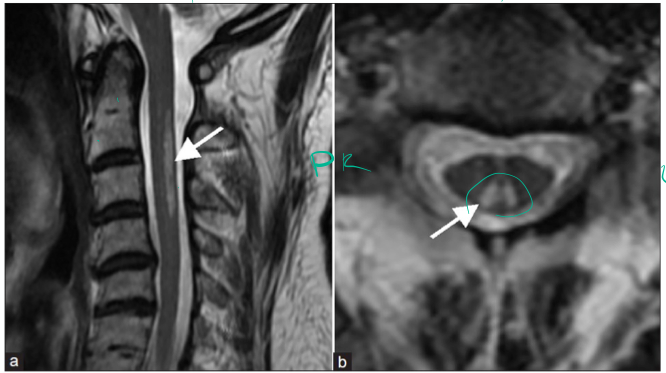

A 30 year old woman presents to the neurology clinic with numbness affecting both of her upper limbs and the upper half of her chest.

Sensory examination reveals she has bilateral loss of pinprick and temperatue sensation in the totality of her C4-T2 dermatomes.

Vibration, light touch and two-point discrimination are preserved.

Can you explain the bilateral nature of her symptoms and signs?

The lesion is found at the ventral white commissure where the spinothalamic system decussate.

Why are there no signs at levels below T2?

Because the lesion don’t extend that lateral and all axons inferiorly will pass laterally.

If the lesion continues to expand, how might her clinical picture change? Think about the location of the somatotopic organisation of the sensory tract.

Might go to lower limbs

Spinocerebellar tracts can be affected.

Motor functions might be affected.